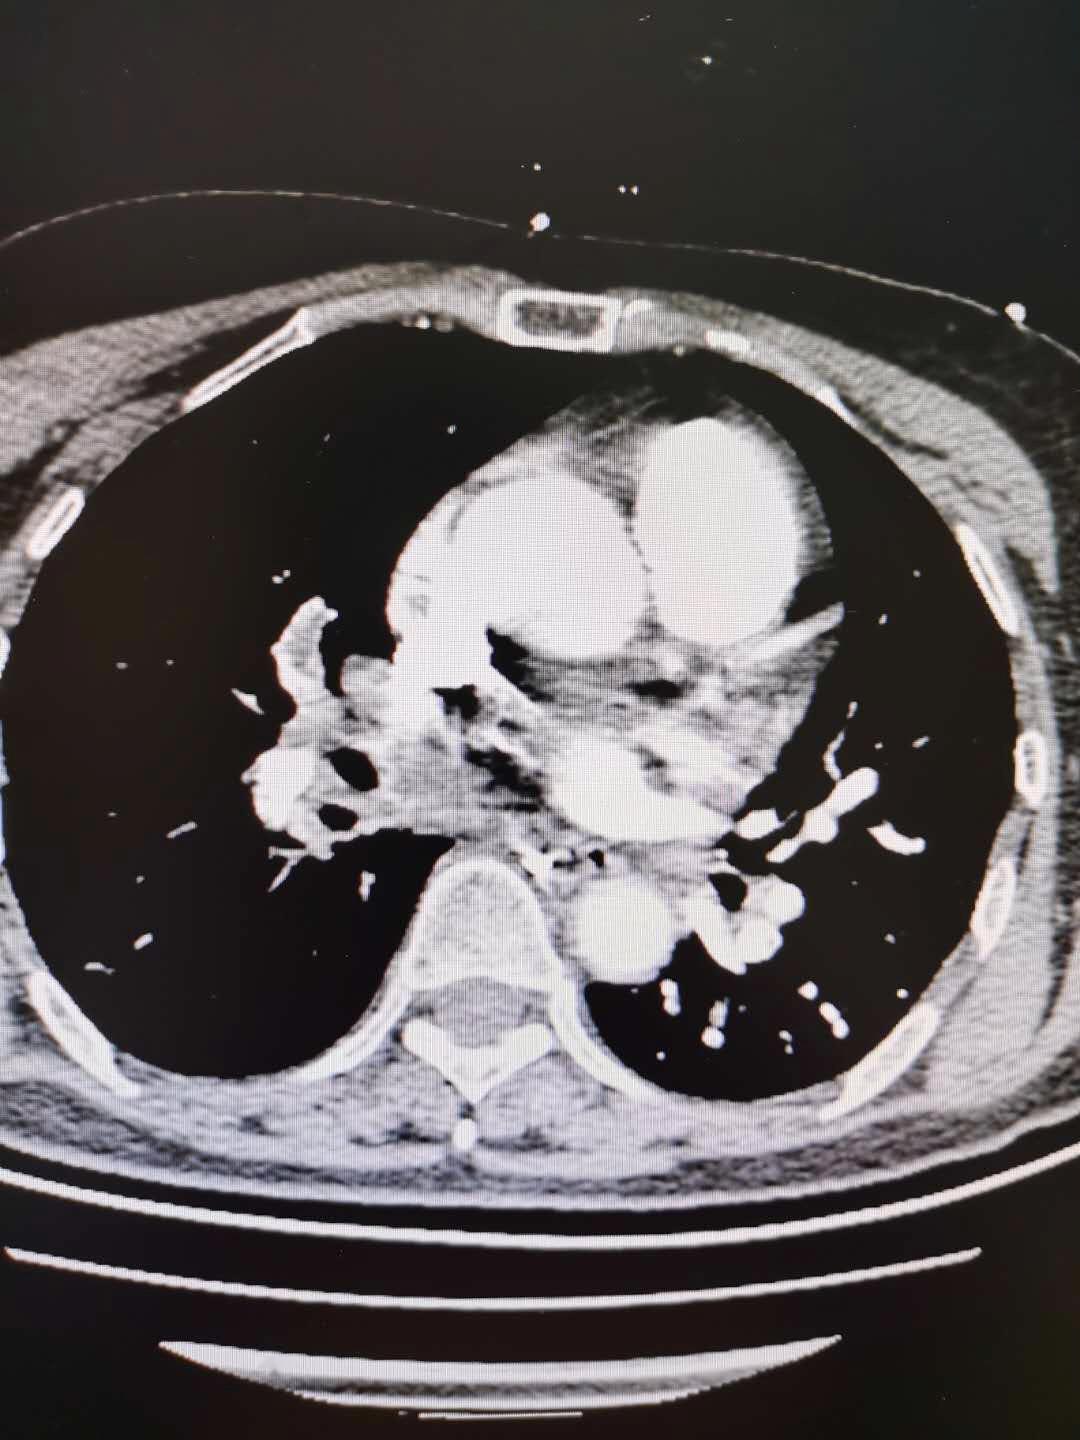

聚焦聊城市二院多学科联合救治急性肺栓塞并高出血风险的梗阻性休克